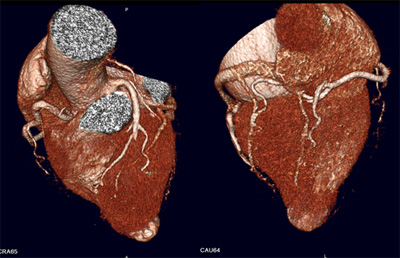

Imágenes volumétricas del corazón y las arterias coronarias obtenidas con Aquillion 64 de Toshiba

A la izquierda vista craneal, donde se elimina la arteria pulmonar permitiendo visualizar el tronco de la arteria coronaria izquierda, la oclusión de la descendente anterior.

A la derecha la vista caudal. En ambas vistas el apex del VI se encuentra deformado por el aneurisma apical